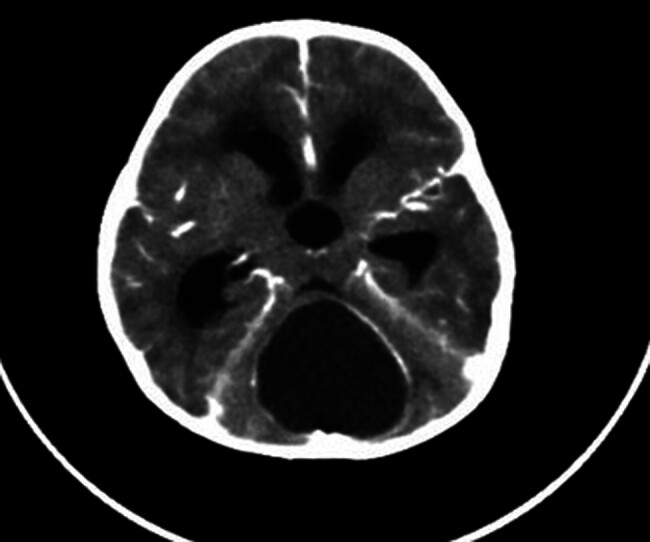

一名2岁的女性患者在经历了全身性强直阵挛性发作并伴有发热后出现意识丧失。她接受了紧急右额部外脑室引流术。术中脑脊液分析感染模式阴性。MRI显示后窝中线主要为囊性病变,伴压缩肿块效应。随后,她接受了枕下开颅术,显微切除后颅窝病变。组织病理学报告角蛋白薄片伴严重活动性炎症,异物型巨细胞反应,头皮切除游离毛轴穿过炎症灶,与毛突窦一致。病人随后健康出院回家。

A 2-year-old female patient presented after experiencing a generalized tonic-clonic seizure accompanied by fever, followed by a loss of consciousness. She underwent an urgent right frontal external ventricular drain placement. Intraoperative cerebrospinal fluid analysis was negative for infectious patterns. MRI showed a predominantly cystic lesion in the midline posterior fossa, with a compressive mass effect. Subsequently, she underwent a suboccipital craniotomy for microscopic resection of a posterior cranial fossa lesion. Histopathology reported keratin flakes with severe active inflammation, and foreign body type giant cell reaction in scalp excision with free hair shafts through the inflammatory focus, consistent with pilonidal sinus. The patient was then discharged home in good health.